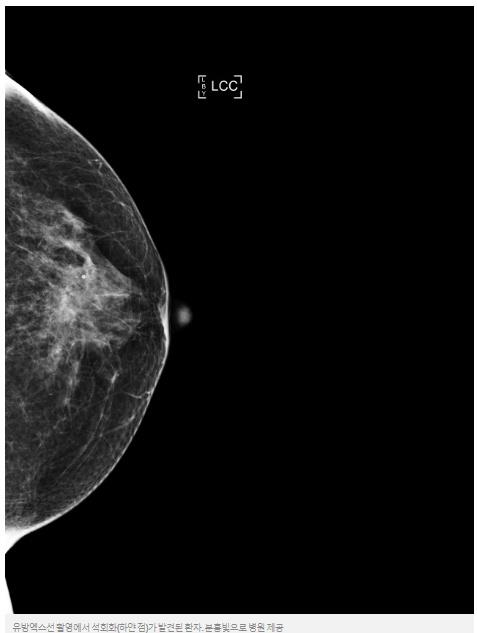

◆유방촬영에서 보이는 하얀 점

유방암 검진을 위해서는 가슴 부위를 압착하듯 눌러 촬영하는 유방 엑스선촬영검사를 받게 된다. 그 결과 석회화가 있다는 의사의 말에 걱정부터 덜컥 앞서는 여성들이 많다. 유방 석회화는 유방 촬영 사진 상 소금가루를 뿌려놓은 듯한 하얀 점들이 보이는 것을 말한다.

유방의 석회화는 여러 가지 원인으로 생겨날 수 있는데 지방세포가 변해서 생길 수도 있고, 염증이나 물혹 안에서 칼슘이 뭉쳐져서 생겨날 수도 있다. 이런 양성석회화는 그냥 놔두면 되고 경우에 따라서는 저절로 없어지기도 한다.

문제는 유방 석회화가 유방암에 의해서도 생겨날 수 있다는 점이다. 이동석 분홍빛으로 병원장은 "암은 정상세포보다 증식속도가 빠른데, 암세포가 증식하기 위해서는 많은 혈액공급이 필요하다"면서 "암세포 덩어리 중에서, 혈액공급이 암세포의 증식 속도를 따라가지 못하는 부위가 있으면 그 부위의 암세포는 죽게 되고, 이것이 유방엑스선촬영사진에서 하얀 점, 석회화로 보이게 된다"고 했다.

이 병원장은 "석회화는 악성도가 높은 암에서 잘 나타나기도 하고, 0기 암인 관상피내암이 석회화의 모습으로 발견되는 경우도 흔하다"면서 "이런 관상피내암은 98%가 완치가능한데, 조기에 발견해 치료하는 것이 중요하기 때문에 의사들이 석회화를 아주 세심하게 들여다보는 것"이라고 설명했다.

석회화는 유방초음파검사로는 잘 보이지가 않고 유방엑스선촬영에서 잘 보이므로, 여성 유방암 검사 시 유방엑스선촬영을 시행하는 것이 좋다.